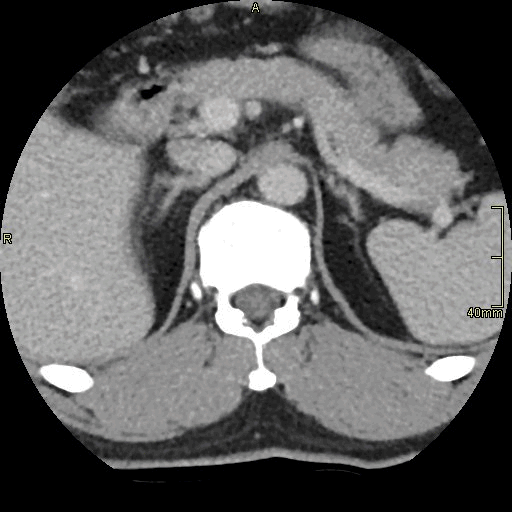

CT Lumbosacral Spine Contrast- Soft tissue window (axial)